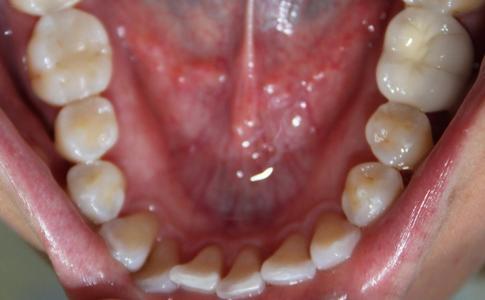

The crowding of this patient's teeth could have led to issues, including buildup of plaque and tartar, harbors harmful periodontal bacteria, risk of periodontal disease, tooth, and bone loss. After one year of Invisalign treatment, teeth have aligned properly for a healthier mouth.

a top-down view of a patients mouth before recieving an invisalign treatment | invisalign dentist vienna va a top down view of a patients lower teeth after receiving invisalign | invisalign dentist vienna va